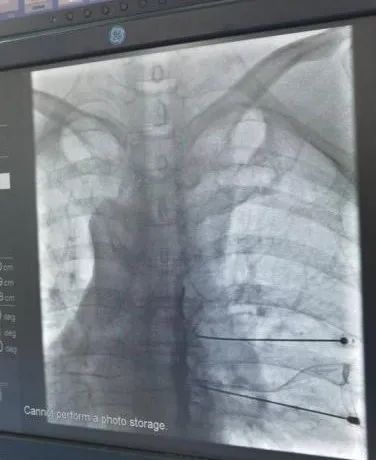

医院以深入合作为契机,医疗服务能力不断提高。其中康复科业务量同比增长20%;内科住院人次同比增长30%;临床检验业务量同比增长18%;内镜中心门诊人次同比增长15%;影像中心业务量同比增长14%。